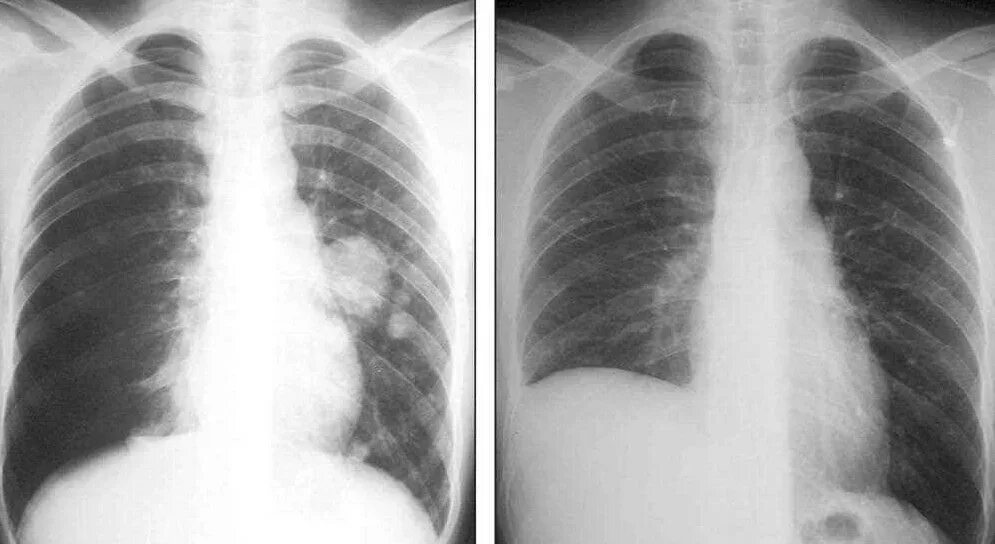

Метастазы в легких терапия